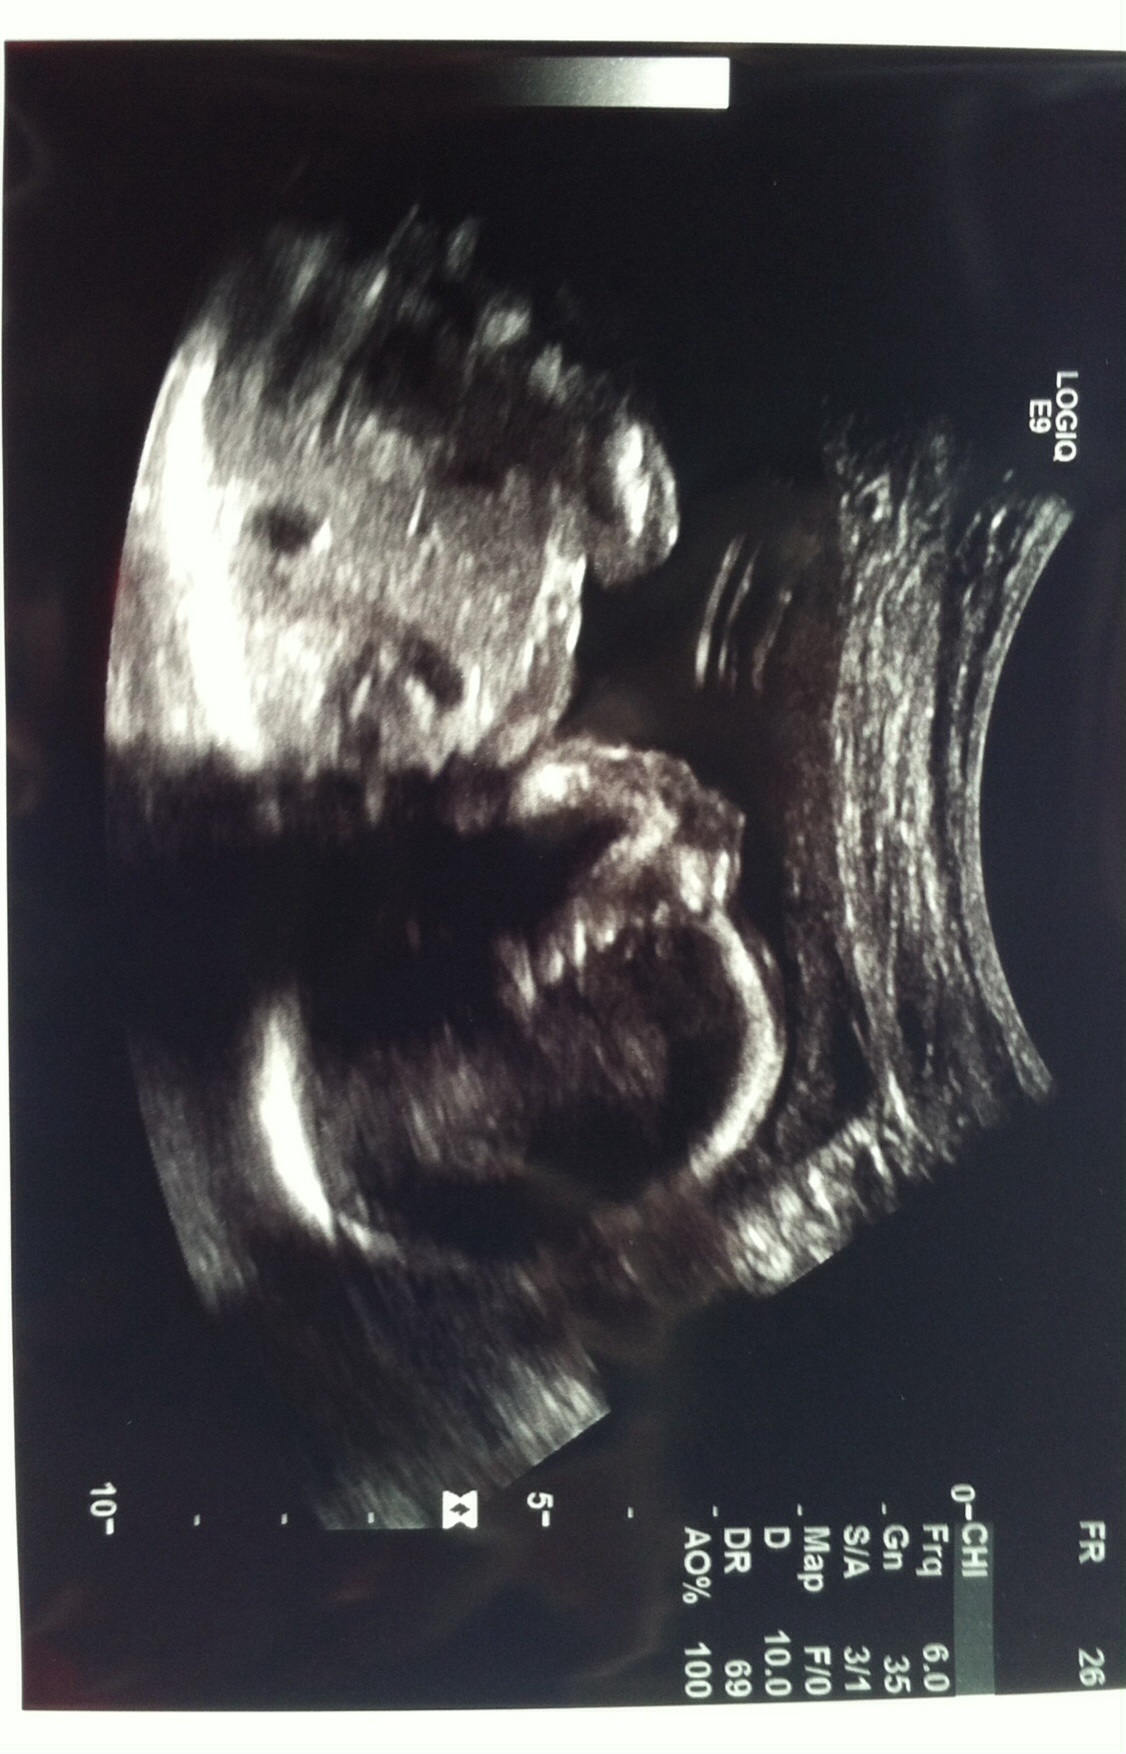

BABY lol still team green over here but after what feels like an eternity, we had a first ultrasound so I thought I would share :)

Sorry for any sideways/upside down or whatever way this posts! Mobile is not my friend lol